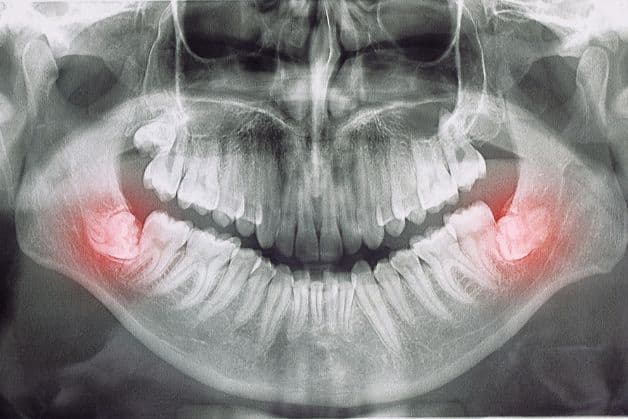

Răng khôn mọc lệch cũng là một nguyên nhân gây đau nhức răng.

– Răng khôn mọc lệch: đây không phải là bệnh lý nhưng nếu răng khôn mọc lệch có thể đâm vào các răng bên cạnh gây cảm giác đau nhức chân răng